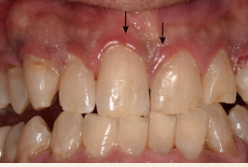

Describe the tissue contour in this image?

Rolled - thickened gingival margin